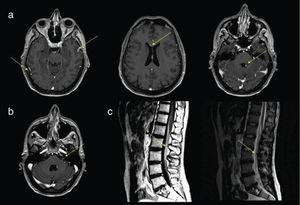

Mujer de 65 años, portadora de linfoma difuso de células B grandes quien presentó falla respiratoria catastrófica por COVID-19. Se inició soporte con oxigenación por membrana extracorpórea. Posteriormente, desarrolló macroaglutinación y trombosis arteriovenosa multisistémica. ¿Qué […]